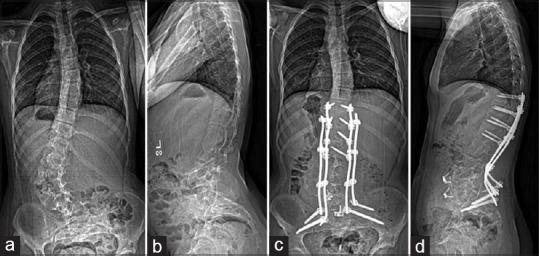

We report the use of computerized tomography (CT)-guided navigation for complex spinal deformity correction (anterior and posterior) in an 8-year-old patient with neurofibromatosis complicated by dystrophic pedicles, dural ectasia, and extensive vertebral scalloping. A retrospective review was conducted of the patient's medical records for the past 3 years, including the patient's office visit notes, operative reports, pre- and 2-year postoperative imaging studies. The patient successfully underwent anterior lumbar interbody fusion from L3-S1 using CT-guided navigation to negotiate the challenges posed by dural ectasia and vertebral body scalloping. One week after the anterior procedure, she underwent navigation-guided T10-to-pelvis posterior instrumented fusion. There were no perioperative or postoperative complications at 2 years. In patients with complex deformities of the spine, including dural ectasia, scalloped vertebral bodies, and decreased pedicle integrity, the use of intraoperative CT-guided navigation can benefit surgeons by facilitating the safe placement of interbody spacers and pedicle screws.

我们报告了在一名8岁神经纤维瘤病患者中使用计算机断层扫描(CT)引导导航进行复杂脊柱畸形矫正(前路和后路)的情况,该患者伴有营养不良性椎弓根、硬脊膜扩张和广泛的椎体扇贝样变。对该患者过去3年的病历进行了回顾性分析,包括患者的门诊记录、手术报告、术前和术后2年的影像学研究。患者成功接受了L3-S1前路腰椎椎间融合术,使用CT引导导航应对硬脊膜扩张和椎体扇贝样变带来的挑战。前路手术后一周,她接受了导航引导下的T10至骨盆后路器械融合术。2年时无围手术期或术后并发症。对于患有复杂脊柱畸形的患者,包括硬脊膜扩张、扇贝样椎体和椎弓根完整性降低,术中使用CT引导导航可通过促进椎间融合器和椎弓根螺钉的安全置入而使外科医生受益。